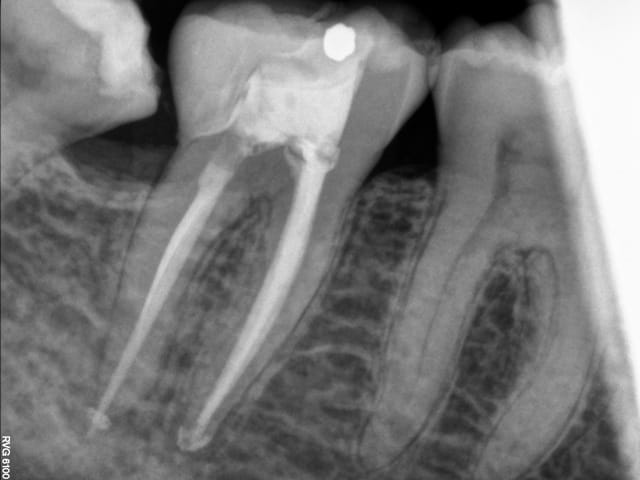

Voilà ce patient a consulté en Juillet pour une douleur à la mastication. Je regarde la radio, belle pêche sous les racines, en bouche, une fêlure traversant la dent dans le sens MD. A votre avis que faire dans ces cas et comment évaluez vous la réussite ou non de l'endo - CCC dans ces cas? Il n'avait aucune douleur quand j'appuyais transversalement de sur la moitié linguale ni sur la moitié vestibulaire (vers l'extérieur de la dent, pour "séparer" les dent).

Bref je fais l'endo, et lisant de plus en plus de choses sur le sans-tenon (surtout le risque de fracture supérieur qu'il engendrait par perte de substance dentinaire) je me suis lancé dans un "Nayyar" core, compo descendant dans les entrées canalaires et par dessus une CCC.

Ci-joint les radios.